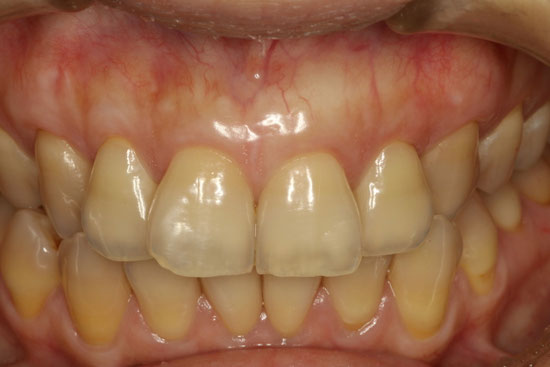

前歯の歯茎が下がってしまっているケース

治療前

歯茎の再生治療後2週間、下がってしまっていた歯茎の部分に歯茎が覆い露出していた歯の根っこが隠れました。歯茎に傷をつけずに歯茎の再生治療を行うことができました。